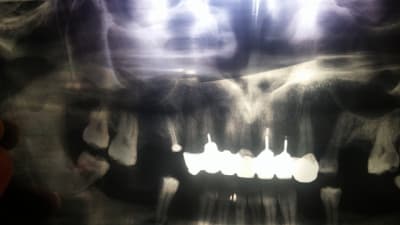

Un patient voudrait refaire son bridge sup car pas très esthétique... Moi j'ai direct reniflé le bon plan!

Je lui demande quand même d'aller faire une pano pour avoir une idée globale des fondations, et c'est le drame.

Bridge réalisé il y a 2-3 années dans son pays d'origine.

Franchement je sais pas par ou commencer?

Oui je vois, mais est ce qu'avec une endo dans les règles 12, 13 et 14 vont s'en sortir?

Ou résection/curetage indispensable?

J'ai déjà viré la 15, et la 16 c’était la semaine dernière.

Aussi, est ce que l'autre prat était inconscient, ou c'est quoi cette technique d'ancrage sans obturation canalaire...?